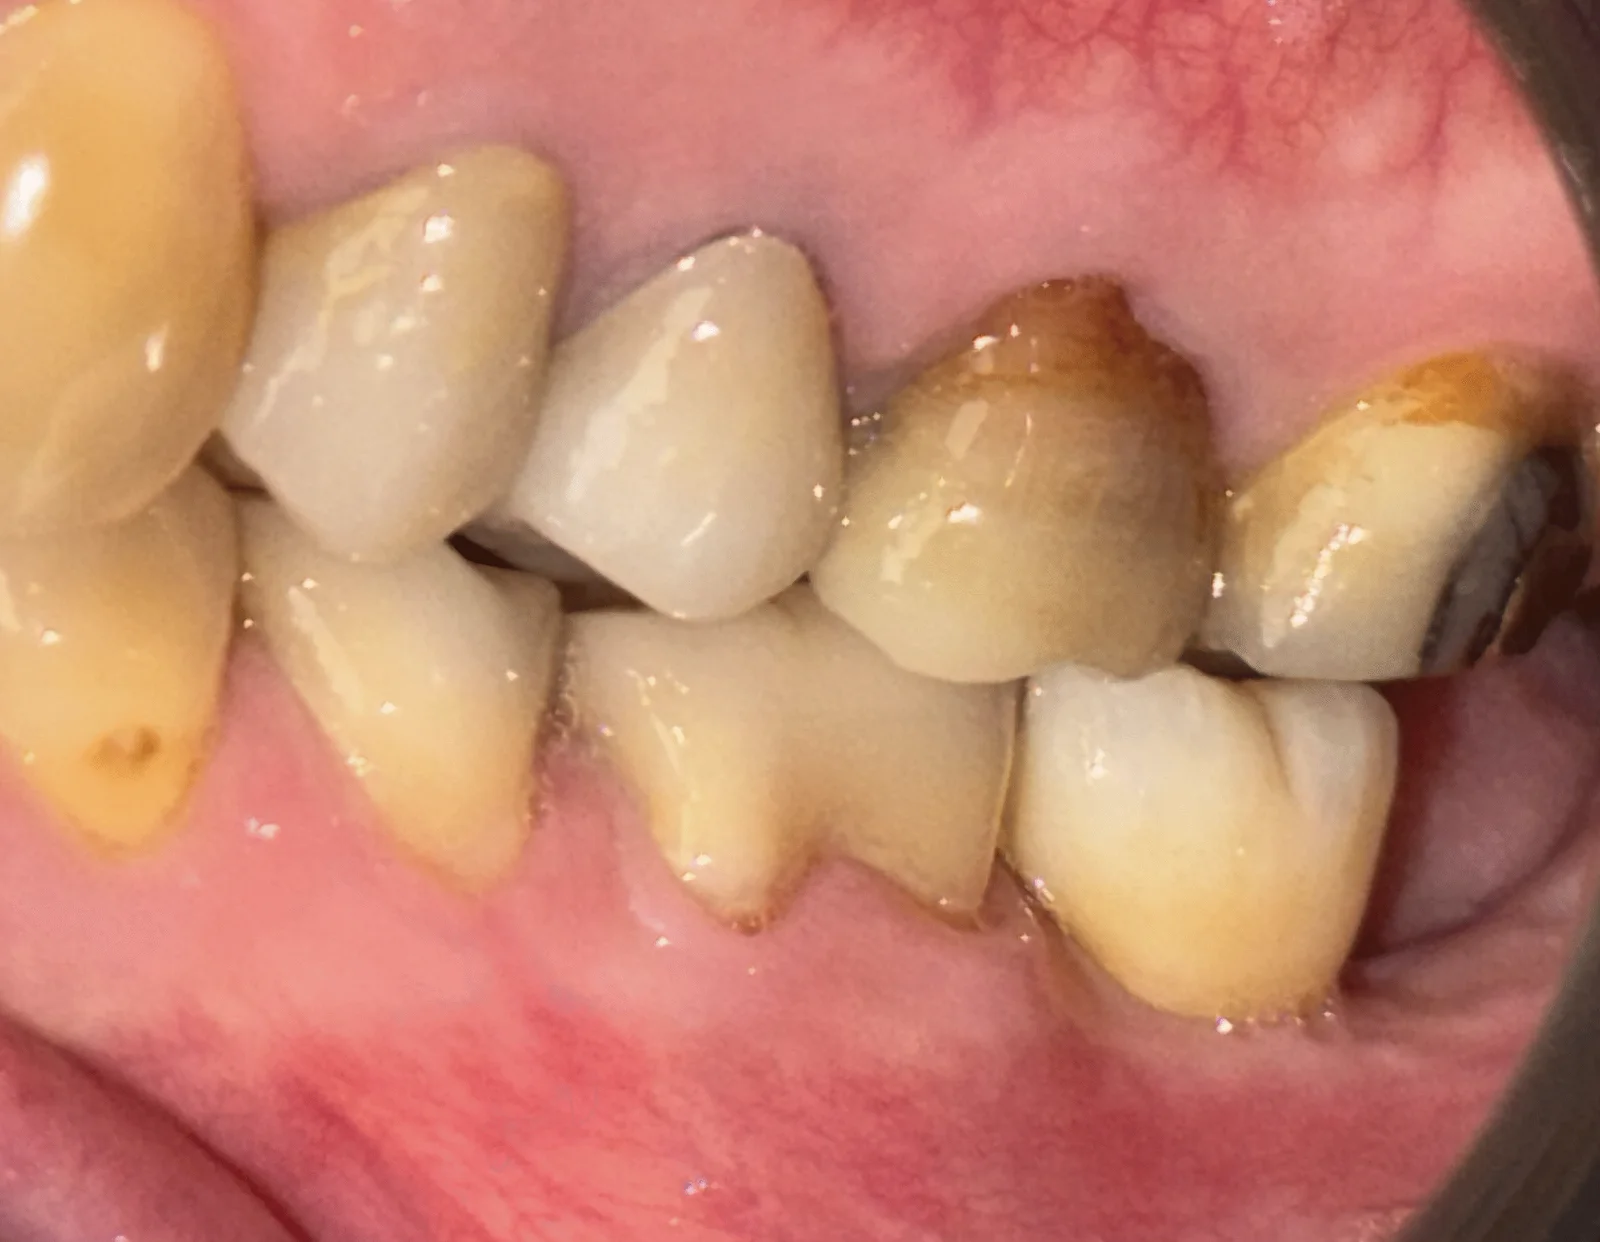

La première consultation vise à établir un bilan global du patient, indispensable pour évaluer l’indication implantaire et anticiper d’éventuelles contre-indications. Cette étape repose sur une anamnèse médicale et dentaire approfondie, un examen clinique complet, et des examens complémentaires standardisés.

Le praticien procède également à un examen bucco-dentaire complet, en évaluant :

- la santé du parodonte (gencives, tissus de soutien) : présence d’inflammation, poches, récessions, mobilité dentaire ;

- l’espace disponible pour la future restauration prothétique (hauteur, largeur, occlusion).

Une fois l’ostéointégration confirmée, la phase prothétique peut débuter. Cette étape consiste à réaliser la ou les couronnes implantaires qui viendront se fixer sur les implants intégrés dans l’os.

Une fois la prothèse réalisée, elle est fixée sur l’implant par vissage ou par scellement, selon les indications cliniques. Le résultat final vise à restaurer non seulement la fonction masticatoire, mais aussi l’harmonie du sourire.